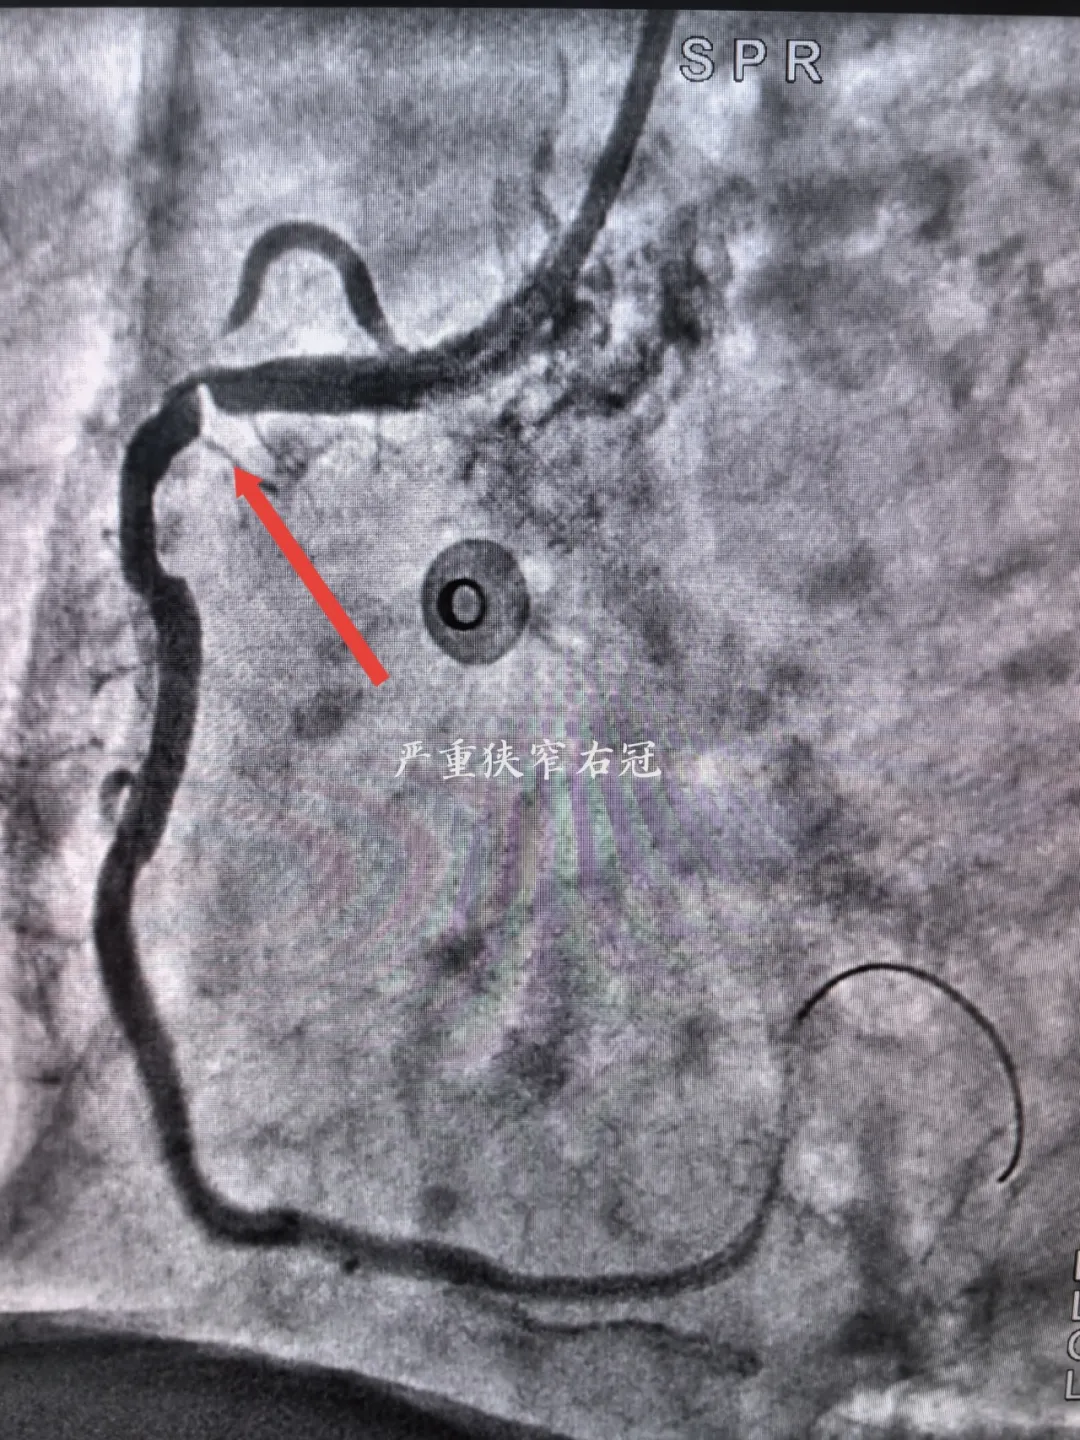

入院完善各項檢查后考慮為冠心病合并右鎖骨下動脈狹窄可能,經(jīng)宋坤青主任團隊研究后,決定為該患者施行冠脈造影+鎖骨下動脈造影。經(jīng)過嚴謹?shù)男g(shù)前討論及充分的術(shù)前準備后,在2024年06月07日上午,宋坤青主任、趙博韜副主任及楊亞楠、冉德聰主治醫(yī)師為該患者進行了造影手術(shù),結(jié)果提示右冠狀動脈近近段90%狹窄,前降支近中段90%狹窄,右側(cè)鎖骨下動脈閉塞。

右冠狀動脈嚴重狹窄